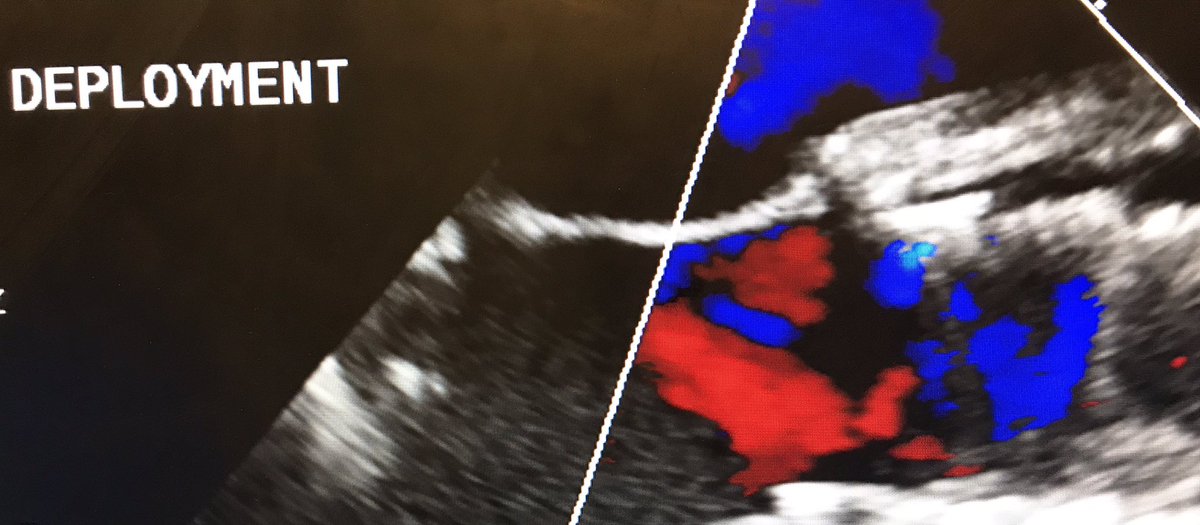

“Learning to Burn” w/ @JasonFoerst on my 1st #Transcaval access. Did #TAVR S3 23: 🚫PVL, mean AVG=2 by Cath, 6 by Echo; Final transcaval w/ minor Ao-C flow, type 1 closure. #CarilionStructural @CarilionSHD @Mjoseph3324 @SulaimanRathore @ShereeEmore @carmenhsalmon